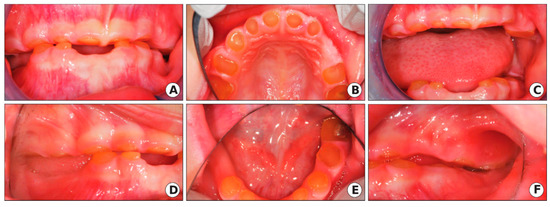

Due to prior ineffective OCS and severe ASD, treatment under General Anesthesia (GA) was accepted as the best method to restore the patient’s oral health. Under GA, a full set of radiographs were taken (Figure 5), along with intraoral photographs (Figure 6), which revealed an irregular/extensive caries pattern extending to the cusp on all permanent first molars due to attrition and poor enamel to dentin strength associated with DGI-II. The patient had amber-hue colored anterior teeth with most enamel missing and attrition down to the gingival margin on all primary first and second molars, and caries were present on the facial surface of all upper and lower anterior incisors as seen in Figure 6.

Figure 6.

Case 2 clinic photos. (A) Pre-op intraoral photo of the maxillary arch. (B) Pre-op intraoral photo of the mandibular arch (mandibular first molars partially visible). (C) Post-op intraoral photo maxillary arch reveals stainless steel crowns (SSC) restorations permanent first molars, facial resin-modified glass ionomer (RMGI) restorations, lingual sealants on permanent incisors, and blood clots at extraction sites of all remaining primary teeth. (D) Post-op intraoral photo mandibular arch reveals SSCs placed on permanent first molars (lower left permanent first molar not visible) and second primary molars, with the extraction of primary first molars and canines. RMGI placed on facial surfaces of anterior incisors.

Primary teeth were extracted due to mobility, as seen in the primary canines and severe, non-restorable attrition in primary molars, except the mandibular second primary molars, which were considered stable enough for stainless steel crowns (SSC) placement. SSCs are thin metal prefabricated caps used to protect multiple tooth surfaces and can be placed in one appointment without the use of a dental laboratory. All permanent first molars were restored with SSC (3M ESPE, St. Paul, MN, USA) due to an atypical caries pattern and poor enamel quality. Anterior permanent incisors were restored with facial surface Fuji II LC, a resin-modified glass ionomer (RMGI) (GC America, Alsip, IL, USA) due to better quality enamel margins and the lingual surfaces of the incisors had UltraSeal XT ® hydro TM sealant (Ultradent Products, South Jordan, UT, USA) placed due to previous food entrapment in the deep lingual fossa of the incisors. At the follow up appointment, the mother said the patient was eating well and following improved oral hygiene due to motivation from the mother and siblings when brushing before bedtime.